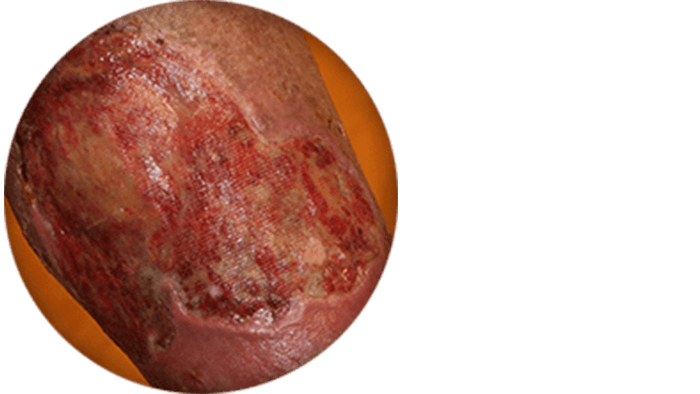

When blood pools in the legs, the skin of the affected area becomes darkened. Itchy skin or eczema may develop as well as a thickening of the skin.

In severe cases, ulcers may develop when pooled blood causes tissue damage.

Swelling, skin changes, and ulcer images courtesy of Dr. Raghu Kolluri.